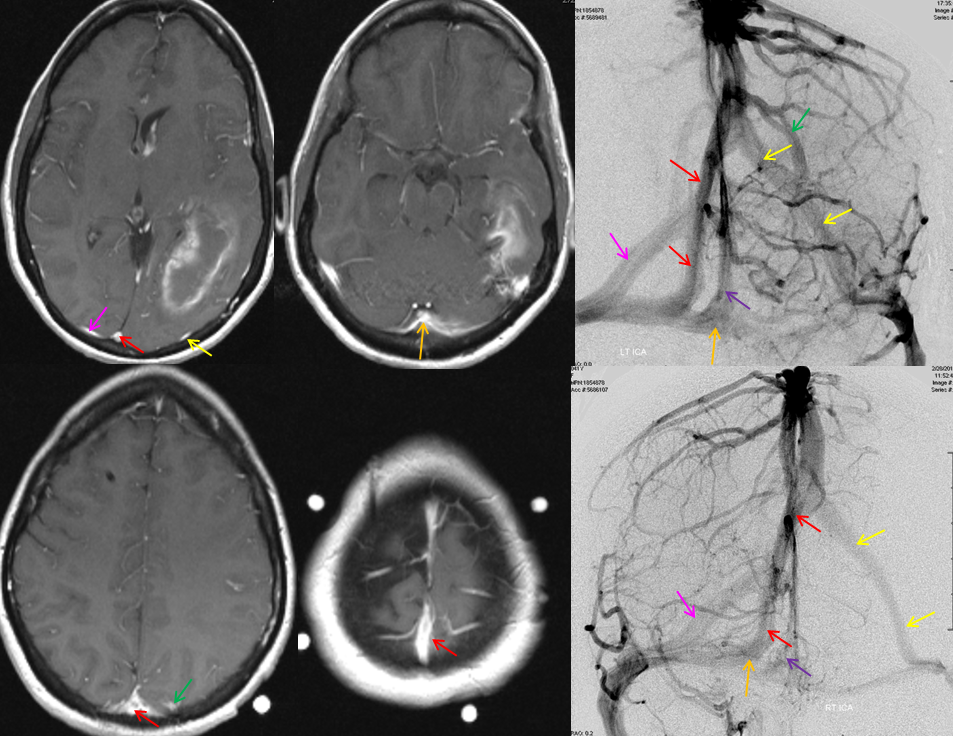

All of the above anatomic knowledge can become very useful in evaluation of venous thrombosis. Numerous collateral pathways develop in this setting attempting to compensate for the loss. The most dramatic cases usually involve the largest channel — the superior sagittal sinus. In this case, a man presented with what initially was thought to be vasculitis-related brain hemorrhage. Subsequent workup led to an angiogram, where sagittal sinus thrombosis with extensive trans-cerebral and trans-osseous emissary vein collateral channels was seen. In retrospect, these findings were present on the patient’s earlier contrast MRI. “Venovibe” or other contrast-enhanced MR venograms can very sensitive, particularly when interpreted with the appropriate index of suspicion. Noncontrast 2-D time of flight MRV I consider to be next to useless as a problem-solving technique. Any thin-slice postcontrast T1 study is vastly superior.